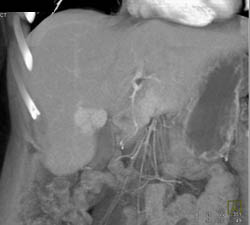

Focal Nodular Hyperplasia (FNH)